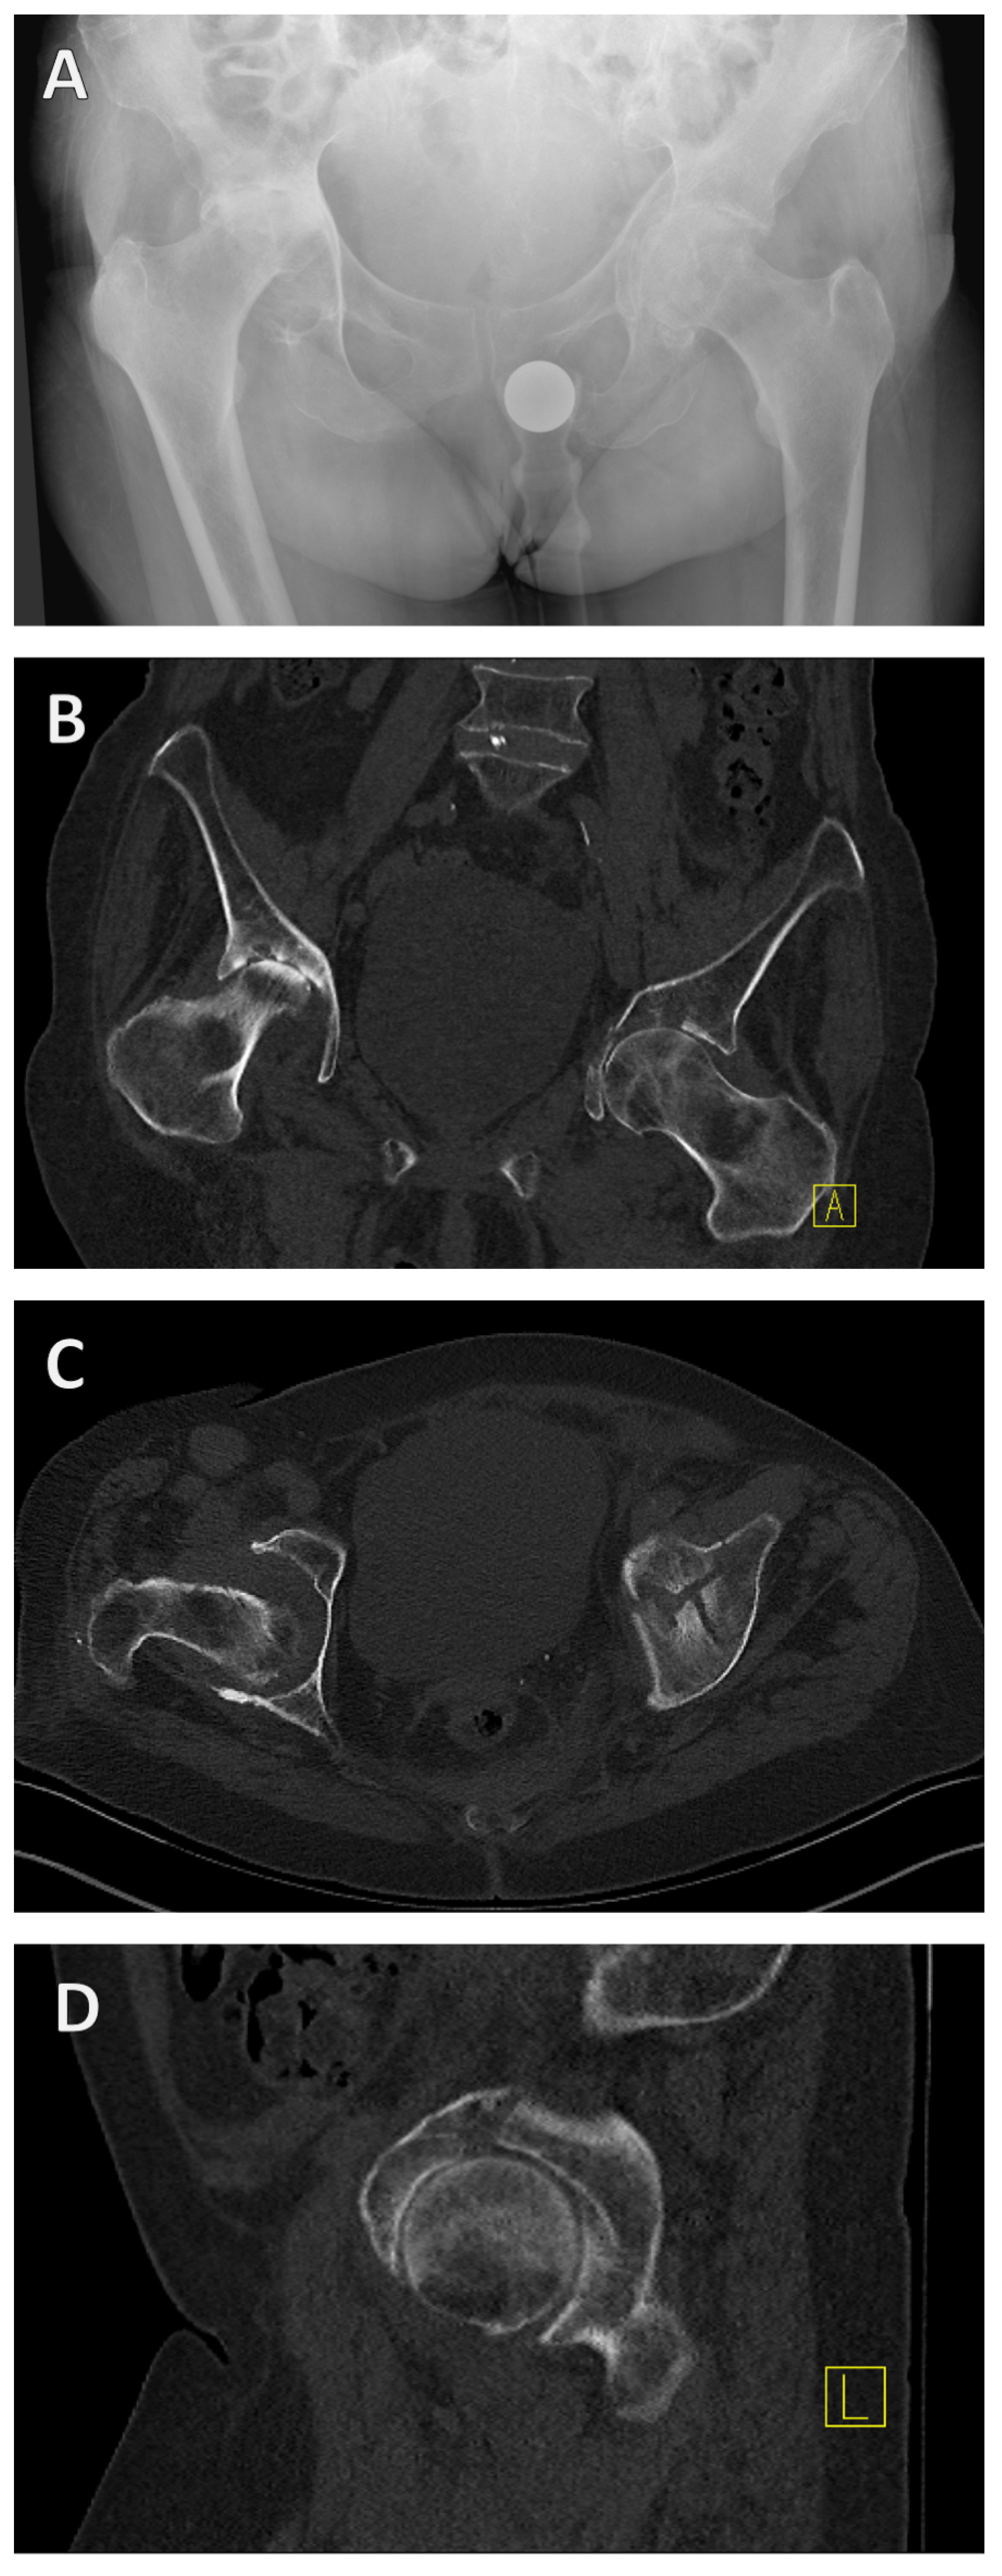

There are currently several classifications for the categorization of acetabular fractures, whereby it can be said that the classification according to Judet and Letournel from 1980 forms the standard in orthopedic and trauma surgery [21,22]. Judet and Letournel classified acetabular fractures into 10 types of fractures according to localization and fracture extension. These were divided into five simple fractures (Figure 2A–E) and a further five combined fractures of different structures of the acetabulum (Figure 2F–J).

Figure 2. Letournel’s classification. A differentiation is established between 5 simple fracture types and 5 combined fracture types. Simple fracture types (A–E) are the fracture of the posterior acetabular rim (A), posterior pillar (B), anterior acetabular rim (C), anterior pillar (D) and the transverse fracture (E). A further distinction can be seen between combined fracture types (F–J): fracture of the posterior pillar and posterior acetabular rim (F), transverse fracture and involvement of the posterior acetabular rim (G), T-fracture (H), anterior pillar with hemivertebral fracture (I) and the two-pillar fracture (J).